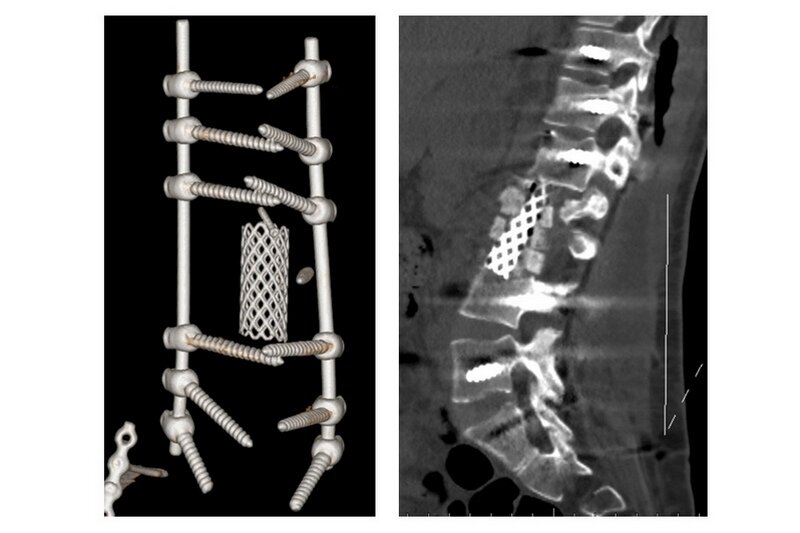

Первые операции ей сделали в Москве и Новосибирске, но через полгода начался остеомиелит позвоночника на фоне перипротезной инфекции. Кроме того, что у пациентки развился воспалительный процесс, в любой момент ее могло парализовать: большой сетчатый имплант на несколько позвонков мигрировал в область позвоночного канала, рассказали в Илизаровском центре.

«Первым этапом мы удалили старую конструкцию из заднего доступа, далее спустя две недели установили новую конструкцию, потом взяли пациентку на третий более сложный ревизионный этап со стороны живота. Удалили ей большой сетчатый имплант, который мигрировал в область позвоночного канала, расширили область декомпрессии и установили новый. Риск операции заключался в том, что при удалении импланта важно было не повредить спинной мозг», — рассказал руководитель группы гнойной вертебрологии Центра Илизарова, врач-нейрохирург Максим Древаль.

Пациентке с ювелирной точностью провели сложнейшую ревизионную операцию. Спустя 2,5 месяца комплексного лечения она благополучно вернулась домой в Кемерово.

Фото: Центр Илизарова